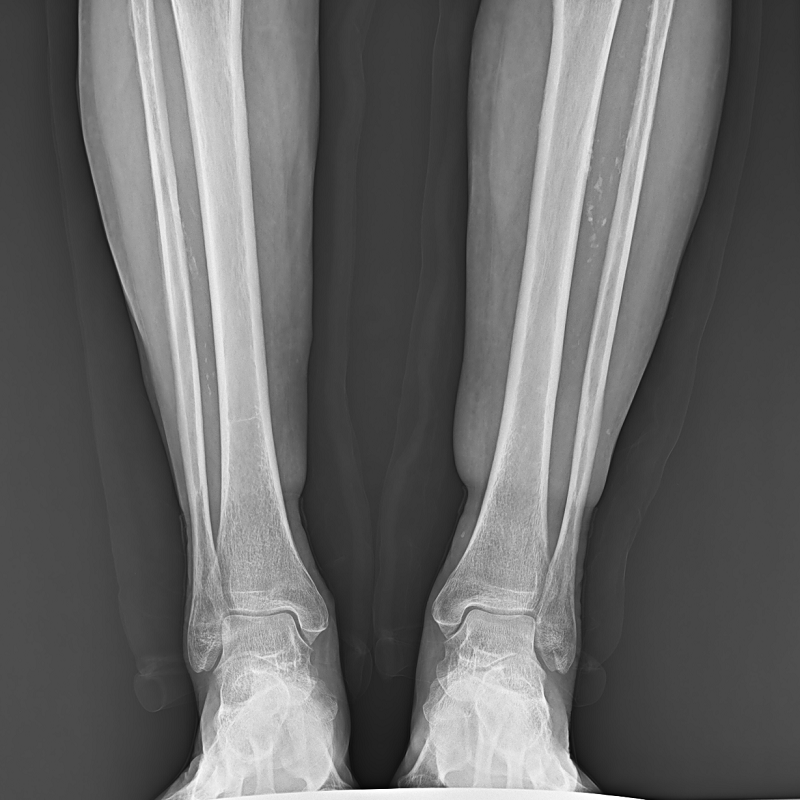

●呈現(xiàn)全下肢或全脊柱圖像

●在脊柱及下肢畸形矯正手術(shù)治療中,為術(shù)前方案制定和術(shù)后復(fù)查提供精準(zhǔn)測(cè)量

●有效解決傳統(tǒng)X光片不能一次成像問(wèn)題,為患者提供更加優(yōu)質(zhì)的醫(yī)療服務(wù)

點(diǎn)片裝置可實(shí)現(xiàn)大范圍縱向移動(dòng),高效完成各部位、全身拼接等檢查需求